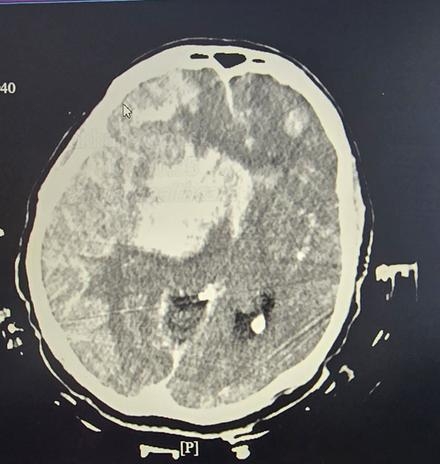

She received systemic tPA for both PE and stroke, underwent RCA thrombectomy, and had a temporary pacemaker placed. Planned mechanical thrombectomy was aborted after imaging showed haemorrhagic infarction, cerebral edema, and herniation. Echocardiography revealed a PFO, suggesting paradoxical embolism. Despite aggressive ICU management, her neurological condition deteriorated, and following confirmation of brain death, care was transitioned to comfort measures.